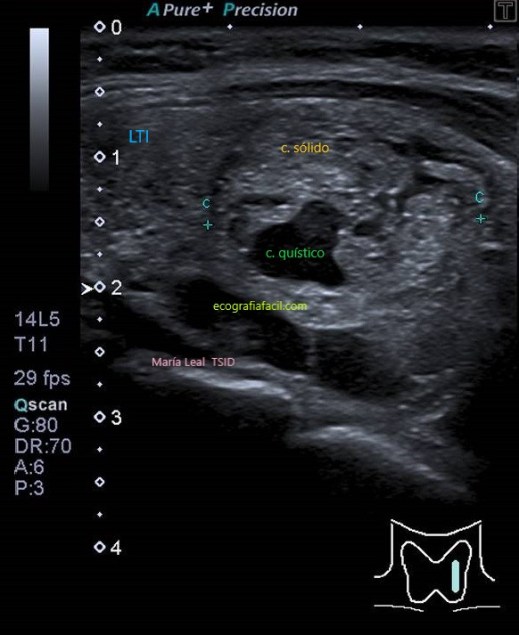

SÓLIDO QUÍSTICO:

Nódulo sólido-quístico